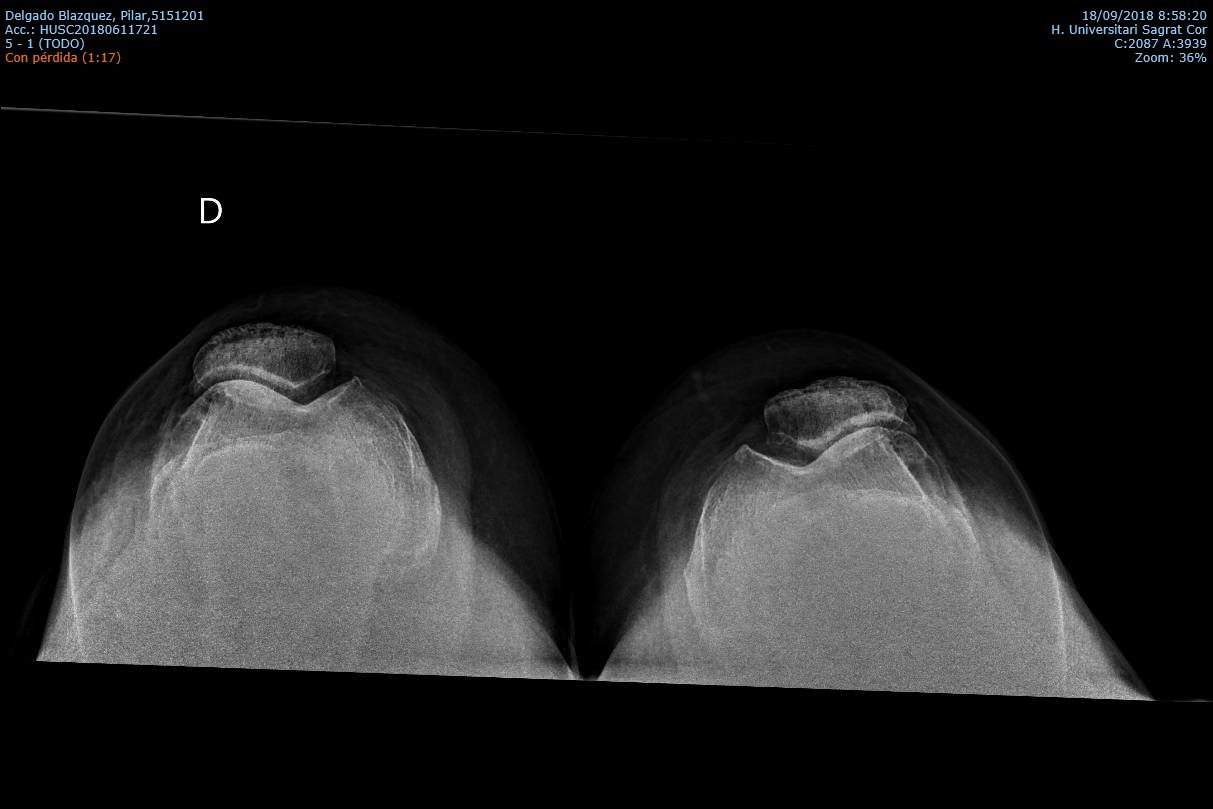

La Prótesis Femoropatelar de Rodilla.

La prótesis parcial femoropatelar de la rodilla es una prótesis especial que está indicado en pacientes con un desgaste muy inicial y con un patrón que afecta solo el compartimiento anterior de la rodilla. Típicamente, son pacientes con dolor en la parte de delante de la rodilla al estar sentados o al subir o bajar escaleras. No les molesta al caminar sobre un terreno plano sin desnivel. Tiene la ventaja de resecar mucho menos hueso del paciente, así preservando más hueso para el futuro. Además, al mantener la parte biológica del cartílago y la ligamentosa de los cruzados de la rodilla, parece conservar mucho mejor la sensibilidad y la marcha de la rodilla (la propiocepción). También la recuperación de esta cirugía (al ser menos agresiva) es más rápida.

|  |  |

Los mejores resultados de supervivencia se ven en pacientes con poca enfermedad y poca deformidad del aparato extensor, mayor de edad o con normo/bajo peso. Los pacientes candidatos a esta protesis probablemente no son más de 2-3 % del total de pacientes con artrosis de la rodilla. Además, su uso es restringido debido a la probabilidad de la progresión de a enfermedad dentro del resto de la articulación, que puede ser generador del dolor y fracaso de la prótesis con el paso de los años. Por tanto, cuando se decide por optar por este implante precisa un consenso claro entre el cirujano y el paciente entendiendo todos los variables que puedan surgir. Siempre que se plantea colocar una protesis femoropatelar habitualmente también se tiene preparado la protesis total por si el grado de enfermedad comprobado durante la cirugía es más de la prevista antes de la cirugía.